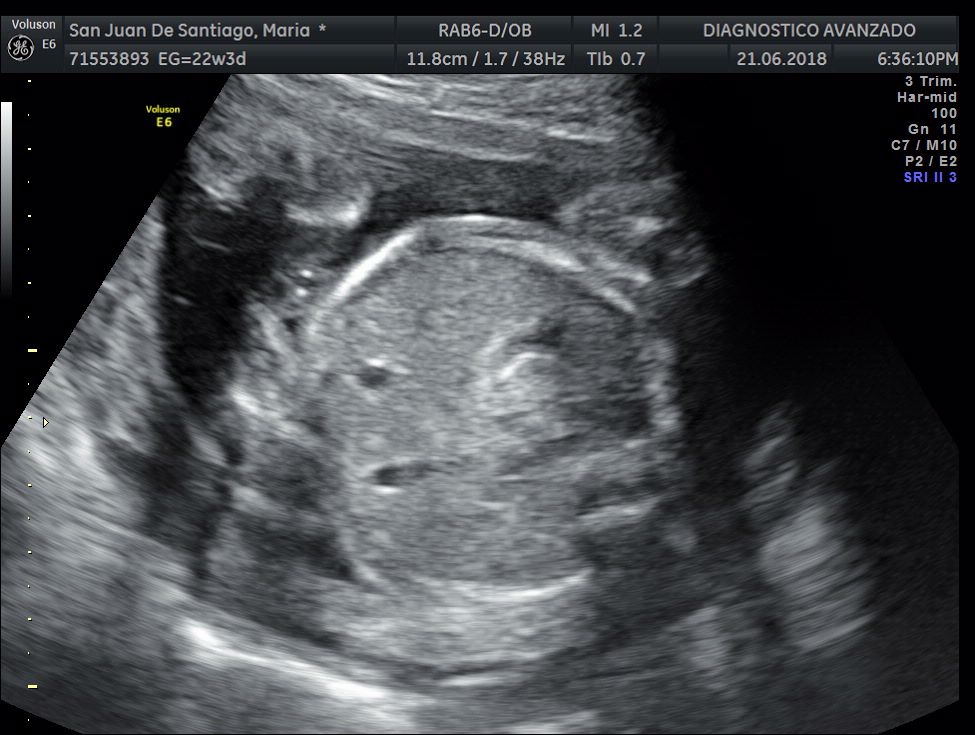

¡Hola a todos! Hoy hemos ido a hacer la tradicional ecografía 3D de la niña, os dejamos todo el material (aunque es un poco demasiado).